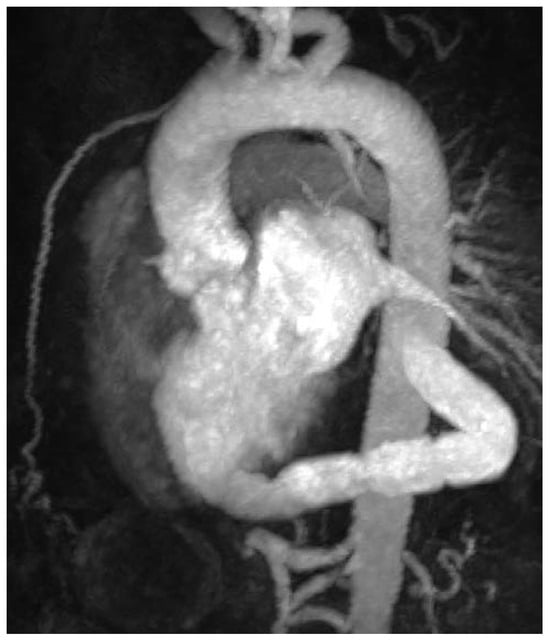

Case report A 22-year-old male experienced a presyncopal spell while studying for a university examination [...]